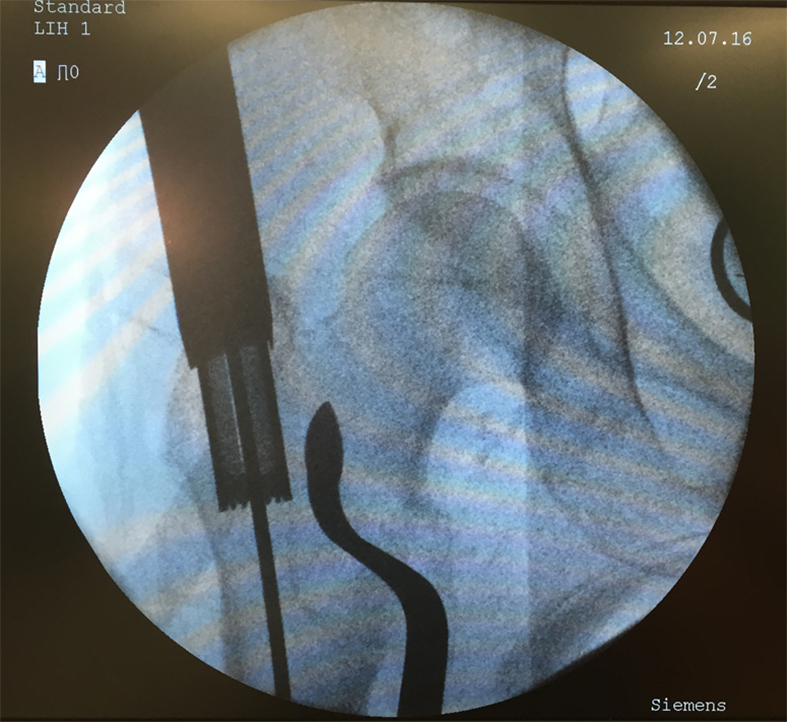

An 83-year-old female patient sustained a 31-A.2.2 fracture of the right proximal femur after a fall at home (Figs 1-2). Intraoperative and postoperative images are shown (Figs 3-5).

A 98-year-old female patient sustained a pertrochanteric fracture of the left proximal femur due to fall in her nursing home (Fig 1). There was significant pain and coxarthritis in the right hip, and hypertension. Surgery was performed within 24 hours. There was an indication for augmentation due to the instability of the fracture. The patient additionally suffered from osteoporosis and dementia.